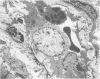

Colonocyte damage in the rectal mucosa in shigellosis is the result of bacterial invasion and leads to ulceration. Additional factors in colonocyte damage may be the Shigella cytotoxin and, especially in colonic crypt cells, bacterial endotoxin. A vascular lesion was present in the lamina propria of the rectal mucosa, which resembled endothelial damage secondary to bacterial endotoxins. In patients with longer duration of symptoms, relative vascular insufficiency, activated lymphocytes, eosinophil and mast cell degranulation, and antibody-mediated colonocyte damage may all play a role.